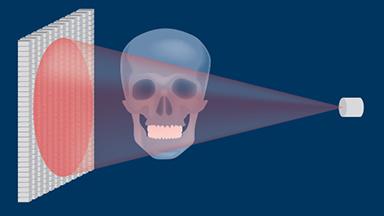

A radiologia é usada em Implantodontia para complementar e confirmar os achados clínicos. As radiografias podem ajudar no diagnóstico, planejamento do tratamento e na revisão de implantes dentários restaurados, em visitas regulares de manutenção. A imagem 3D mostrada aqui demonstra o nível de detalhe que pode ser obtido. No entanto, toda a radiação - incluindo raios-x - acarreta risco de danos aos tecidos e efeitos a longo prazo. Portanto, deve-se considerar os riscos associados à investigação onde a radiografia é planejada, que devem ser equilibrados com os benefícios esperados. Da mesma forma, deve-se considerar uma avaliação das necessidades de diagnóstico e planejamento do caso. A seleção da técnica radiográfica correta deve basear-se no equilíbrio entre as necessidades diagnósticas e o risco.